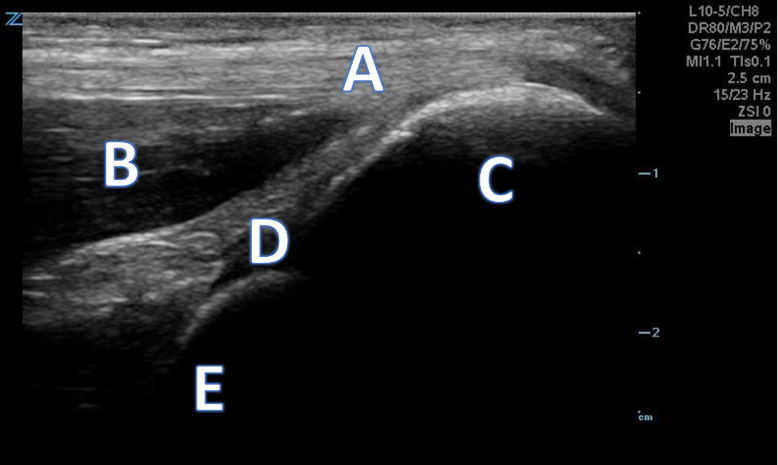

A 66-year-old male with right anterior elbow pain, ecchymosis, and a “lump” in his right upper extremity after a ground level fall.